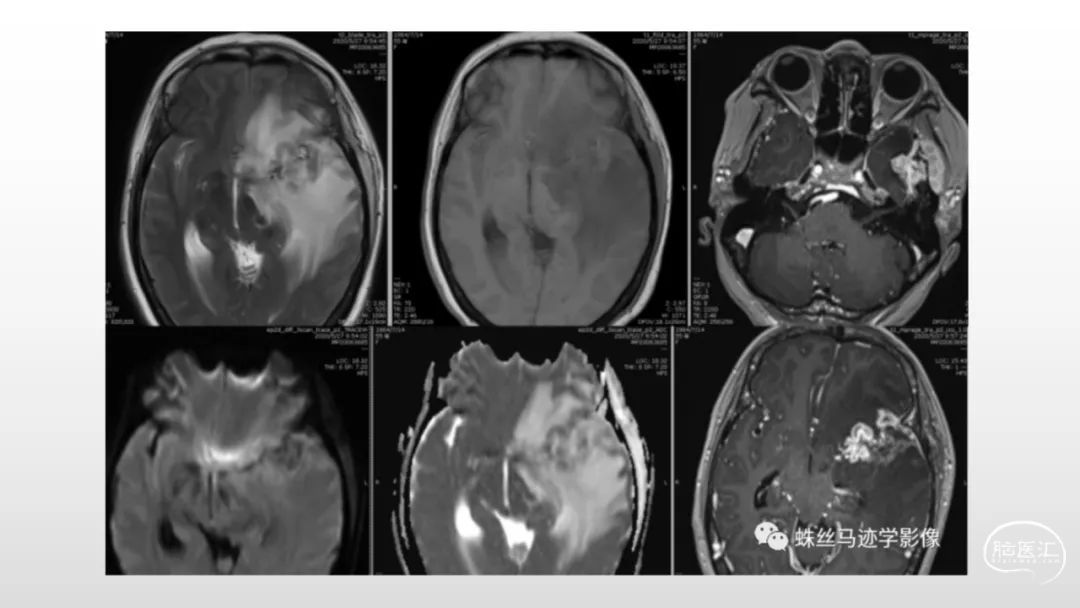

颅脑影像诊断基础知识讲座:脑膜病变